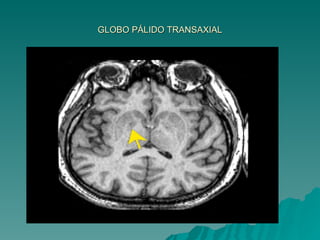

GLOBO PÁLIDO TRANSAXIAL

LENTIFORME = FORMA DE UMA CASTANHA DO PARÁ Não aparece na superfície ventricular – Profundo Medialmente se relaciona com a cápsula interna  Separa do caudado e do tálamo Lateralmente  córtex da ínsula, separado pela  substância branca e pelo claustrum DIVIDIDO – Putamem = lâmina medial Globo pálido = lâmina mais lateral e branca  Coloração mais clara = fibras mielínicas que a atravessam PARTE EXTERNA GLOBO PÁLIDO  lâmina medular  medial PARTE INTERNA

LENTIFORME = FORMADE UMA CASTANHA DO PARÁ Não aparece na superfície ventricular – Profundo Medialmente se relaciona com a cápsula interna Separa do caudado e do tálamo Lateralmente córtex da ínsula, separado pela substância branca e pelo claustrum DIVIDIDO – Putamem = lâmina medial Globo pálido = lâmina mais lateral e branca Coloração mais clara = fibras mielínicas que a atravessam PARTE EXTERNA GLOBO PÁLIDO lâmina medular medial PARTE INTERNA